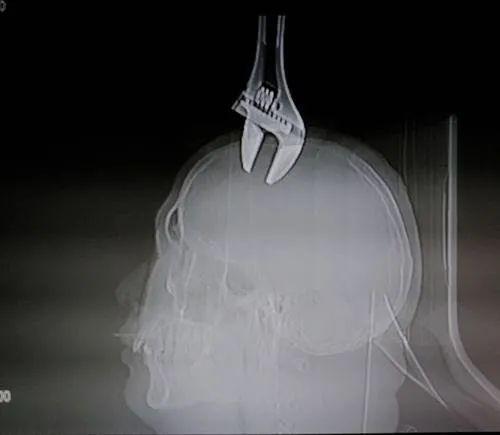

医院拍片显示

这个15厘米长的扳手

插入人的头部2厘米!

天降扳手!入颅2厘米